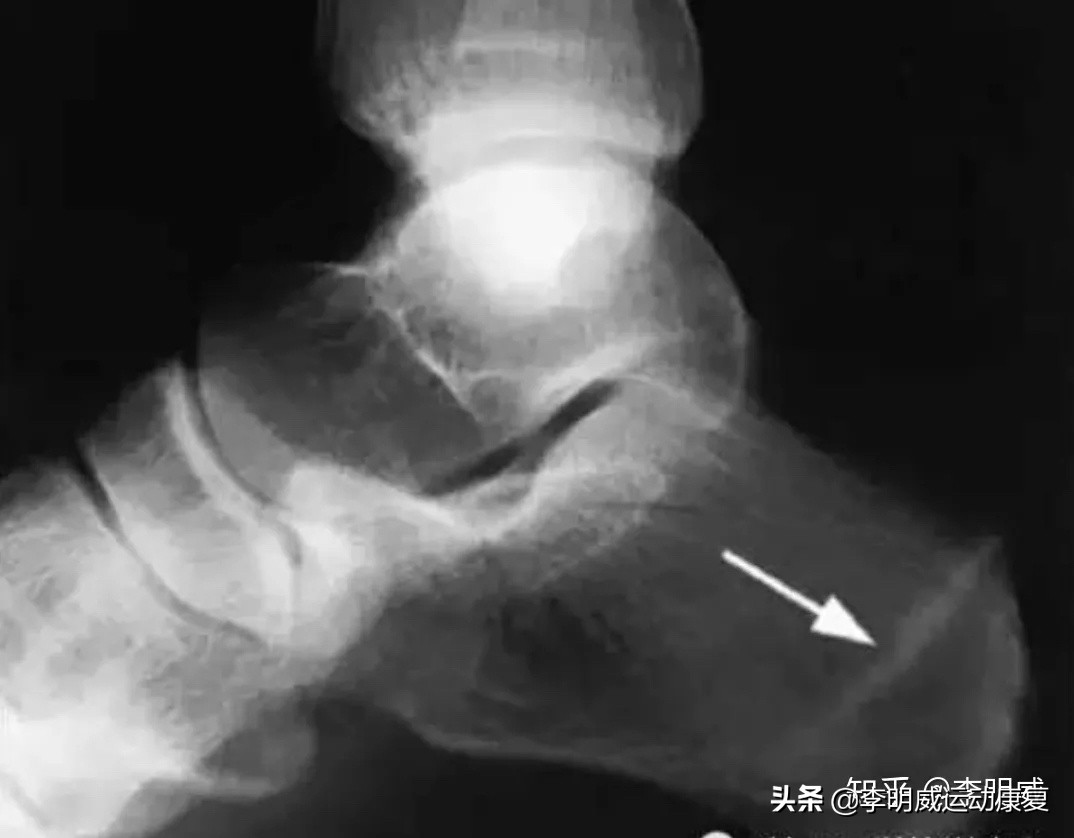

正常情况下,我们的足跟下方,有一个富含脂肪的组织,但由于年龄的增长,负重等,水份、胶原及弹性的下降,这层组织就变薄了(即EF这个距离变薄),足底压力增大,最终导致疼痛。